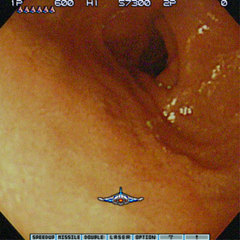

さて先日、予てから念願であった胃カメラを呑んだわけだが、ただひとつ心残りだったのが、自分の胃の映像を入手できなかったコトであった。しかしウチの会社では、人間ドックや胃カメラなどの重度の検診を実施した場合には、後日、担当医に正式な結果を伺いに行くというシステムがあるのである。オイラの場合、パッ見でなんともないことが判明したので、既に当日「キレイな胃ですね」という所感を頂いているが、そういう結果でない場合には、後日に改めて詳細な結果を伺うワケで……まぁ、なにしろ、今朝はワクワクしながら医療センターに向かうのだ。念のため、カルテをもらえなかった場合に備え「デジカメを忘れずに」である。

しかし、イザ先生と向き合うと先生はうかない顔をして、オイラと視線を合わせようとしない……などというコトもまったくなく「コレが食堂で、コレが胃、コッチは十二指腸」などと、フルタニアン・マジカル・インターナル・ツアー状態である。あぁ、楽しい。

やっぱり再度「問題ないです」という結果を受けつつ、カルテを渡される。このカルテを受付に提出すれば診察終了なのだが「このカルテを撮影しないテはないッ!!」のである。すかさず待ち合い室のソファに胃の映像のプリントを展開し、準備してきたデジカメでバシバシと撮影していると……

……などとイキナリ看護婦さんがッ!! な、なにやってんですか!? い、いやなに、記念にと思って……。そ、そうですか……いつもデジカメ持ち歩いてるんですか? あ、今日はコレを狙って用意してきたんです、だってカルテもらえませんよね。そ、それはダメですけど……。いやぁ、コレを機に自分の内面を見つめなおそうと思ってまして……あは、あはは、あはははは(笑)。

ちゅーわけで、ちょっと呆れられながらも、無事、自分の胃の写真をゲットしたのであった。ただ、そのまま載せるっつーのも、いくらなんでもちょっとアレなので、照れ隠しに「沙羅曼蛇」っぽくしてみるのである。Destroy them all!!